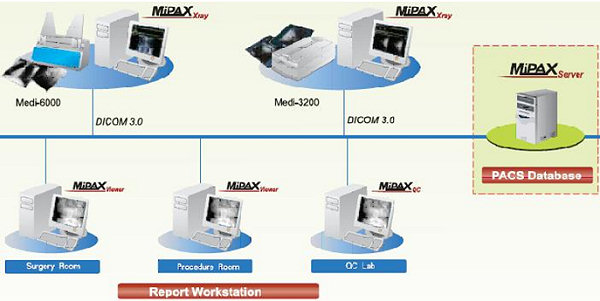

CAD/CAM Services, Inc. medical division scans all types of X-rays. We can scan up to 14 x 17″ film and recognize down to a 44mm Spot size. We support most any Picture Archiving and Commnication Systems (PACS) system, including those from Cemax-Icon’s division of Eastman Kodak, GE Medical Systems, Marconi Medical Systems (formerly Picker Medical Systems), Mitra Imaging Incorporated, and Siemens Medical Systems.

Image compression has always been important and a significant bottle neck in Picture Archiving and Communication Systems (PACS) systems. We therefore directly support DICOM, and a new emerging standard from LizardTech that is offering up to 50-1 image compression! This allows a standard size film to be reduced to less than a one (1) megabyte image! This directly relates to quickly sharing loss less images over the Internet, and other departments.

Our system, technology and process can eliminate most or all network and traffic problems when you consider a PACS system. Imagine having 60,000 X-ray images all on-line, and immediately accessible to your remote doctors, and storing everything on a single 45 GB hard drive!

In addition to working with your existing PACS system, CAD/CAM Services Medical Division has also written custom applications for radiologist needs, and review / clinical conferences. Please contact a specialist about your specific applications.